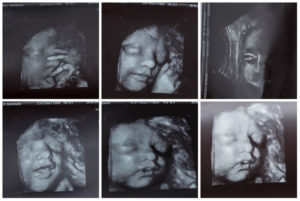

УЗИ будущая мама должна сделать во время второго скрининга, если она не успела, то только в этом случае ее могут направить на ультразвуковое обследование на 24 неделе. Обычно, второе исследование мама проходит на 18 неделе беременности. По данным УЗИ можно уже многое узнать о будущем малыше.

УЗИ предоставит информацию о процессе развития всех внутренних органов малыша, качественный и количественный показатель околоплодных вод, а также двигательную активность и сердцебиение малыша. Фото УЗИ на 24 неделе беременности вы можете посмотреть в фотоподборке в конце статьи.

24 недели беременности фото УЗИ

УЗИ 24 неделя